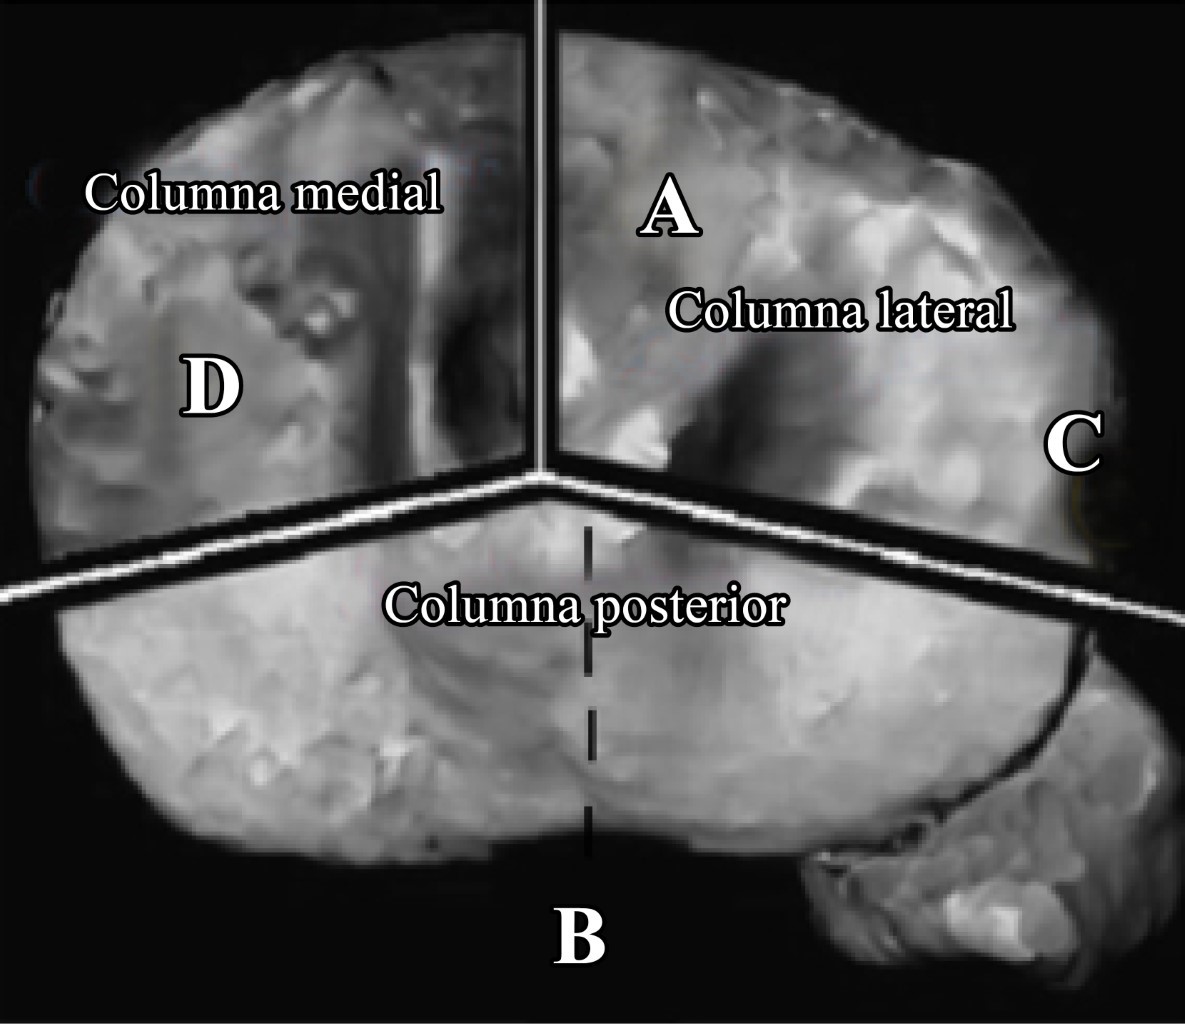

Introduction: tibial plateau fractures affect functionality of a large load bearing joint such as the knee, due to its multiple compromises, not only articular but also the ones including soft tissues. This study aims to evaluate the stability, function, alignment, associated injuries and complications of the knee after surgery and tibial plateau fractures rehabilitation. Material and methods: a descriptive prospective observational study was carried out where patients with a tibial plateau fracture who had undergone surgery, that accomplish the inclusion criteria were included, in the period from April 2018 to June 2019. Analysis of variables was performed with t tests for independent samples. Results: from a total of 92 patients with tibial plateau fracture, 66 (71%) were able to achieve the minimum six months follow-up. The most common fracture according to Schatzker classification was type II with 33.3%, and the most common according to Luo classification was the medial, lateral and posterior three column with 39.4%. More than 70% of patients who underwent surgery due to tibial plateau fractures developed soft tissue injury, therefore knee instability, specially with a higher rate of anterior cruciate ligament injuries or anterior instability. Conclusion: an important proportion of patients who underwent surgery for tibial plateau fractures have knee ligament injuries.

7. Luo CF, Sun H, Zhang B, Zeng BF. Three-column fixation for complex tibial plateau fractures. J Orthop Trauma. 2010; 24(11): 683-92.

Figure 1